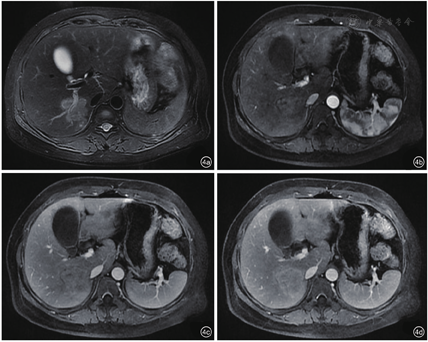

患者,女性,45岁,因糖尿病行体检无意间发现肝右叶肿物3 d入院。无腹痛、腹胀,无寒战、发热,无皮肤、巩膜黄染,无乏力,无体重减轻等。既往2型糖尿病病史,注射胰岛素治疗,血糖控制良好。无肝炎病史,无牧区居住史,无饮酒史,无肿瘤家族史。查体:体温36℃,肝、脾肋下未触及,腹平软,移动性浊音阴性。实验室检查:白细胞计数10.29×109/L,肝功能正常,乙型肝炎表面抗原和核心抗原阴性,甲胎蛋白(alpha fetoprotein,AFP)、糖类抗原19-9(carbohydrate antigen 19-9,CA19-9)及癌胚抗原(carcino-embryonic antigen,CEA)均阴性。腹部超声示:肝脏回声均匀,肝右叶被膜下探及低回声,约5.9 cm×3.6 cm,形态不规则,边界不清,周围无声晕,后方回声未见增强,内未见明显血流信号(图1)。超声诊断:肝右叶肿物,声像图不支持典型肝癌,血管源性病变待排。静脉团注2.4 ml声诺维造影剂,肝脏超声造影示:肝右叶上段可见一大小为5.3 cm×3.4 cm的弱回声团,形态不规则,超声造影呈动脉期高增强,门脉期及延迟期低增强,呈"快进快出"模式(图2)。超声造影诊断:肝右叶实性占位,倾向恶性,建议超声引导下穿刺活检明确性质。腹部CT示:肝右后叶肿物,边界不清,大小约4.1 cm×4.8 cm,分叶状,肿物密度欠均匀,平扫为低密度,增强扫描呈轻度延迟强化,病变侵犯门脉右支分支,致管腔狭窄,管壁水肿(图3),倾向炎性肉芽肿性病变,与肿瘤待鉴别,建议穿刺活检。腹部MRI示:肝右后叶肿物,范围约3.6 cm×4.8 cm,分叶状,边界不清楚,T1加权像(T1 weighted image,T1WI)低信号,T2加权压脂像(T2 weighted image/fat suppression,T2WI/FS)稍高信号影,弥散加权成像(diffusion weighted image,DWI)高信号,增强扫描轻中度延迟强化,病变侵犯门脉右支分支(图4)。腹部MRI诊断:肝右后叶肿物,考虑肝癌可能性大。临床初步诊断:肝右叶实性占位,肝癌待排。患者行超声引导下肝肿物穿刺,组织病理学回报:可见梭形细胞增生,伴炎细胞浸润,结合免疫组化,考虑炎性肌纤维母细胞性病变(图5)。免疫组化结果显示:AE1/AE3(-),Vimentin(3+),Actin(1+),SMA(2+),Desmin(-),s-100(-),CD1a(-),CD21(-),CD35(-),CD68(3+),Ki-67(10%)。患者定期复查,未行治疗。5个月后复查腹部MRI示:原肝右后叶肿物,现已显示不明确,仅局部可见小片状异常信号,T1WI低信号,T2WI/FS低信号,DWI无明显扩散受限,增强扫描强化程度低于周围肝实质(图6),符合良性病变,请结合临床及病理。结合既往穿刺活检及影像学随访病灶消退病史,患者最终诊断为肝脏炎性肌纤维母细胞瘤。随访至今21个月,患者一般情况良好,无复发。

HIMT的超声、超声造影及CT、MRI影像表现多样,可能与不同病灶中病理组织学成分的比例及分布的差异相关[8]。超声常表现为单发、低回声肿块,内回声不均,形态多不规则,在特定切面可呈葫芦状、花生状或多结节融合状等特征性形态,部分病灶周围呈宽带状高回声[9],常无晕环,病灶后方多无明显增强或衰减。由于HIMT中纤维组织增生与慢性炎细胞比例不同,病灶凝固性坏死成分存在差异,随着病程的变化,其声像图表现多样。莫国强等[9]随访7例HIMT病灶发现,3例原低回声病灶内出现高回声,2例原病灶周边低回声晕消失并在11个月后为高回声圈替代,考虑为病变后期或陈旧性病灶内纤维组织增生、形成假包膜所致。本例患者肝脏肿瘤形态不规则,边界不清,与既往报道一致,结合穿刺病理,考虑肿瘤为病变后期,以增生为主。彩色多普勒血流显像(color Doppler flow imaging,CDFI)示肿块内多无明显血流信号,少数内部及周围可探及血流,血流阻力指数(resistance index,RI)多小于0.5[7]。由于不同病灶内新生血管血供程度不同,病灶内纤维化及炎性细胞成分有差异,HIMT超声造影模式亦可呈多样性,但文献报道[10,11],多数HIMT超声造影表现为恶性肿瘤增强模式,即"快进快出",因而超声造影有此模式者并不能完全排除HIMT可能。本例患者肝脏超声造影即因呈现"快进快出"灌注模式而被误诊为恶性。HIMT的CT影像学大多表现为肝内低密度肿块,其强化方式多样,有全瘤填充型、边缘强化型、分隔强化型、无强化型[12]。其特征性改变为动脉期病灶无强化或强化不明显,静脉期及延迟期不同程度、不同方式强化,即呈"慢进慢出"表现,以周边环状强化最多见[13]。本例患者CT表现为边缘延迟强化型,与既往研究相符。MRI平扫病灶多为圆形或类圆形,T1WI常呈低信号,T2WI呈中高信号,推测与病变处于进展期,以慢性炎细胞浸润为主,组织含水量较高有关,MRI与CT强化方式及程度相似,多表现为周边延迟强化[12]。有学者认为,此影像学表现体现了HIMT病理学特点,即病变以门静脉供血为主,肝动脉供血较少[14],病灶门脉期及延迟扫描边缘明显强化,考虑为造影剂从血管内渗透到血管外间隙后,聚集到纤维组织内,从而难以立刻廓清、导致延迟所致[15],病灶中心无强化反映了肿瘤内部细胞可能发生凝固性坏死。本例患者MRI表现T1WI低信号,T2WI稍高信号及周边延迟强化模式,与既往研究一致。HIMT超声造影模式与CT和(或)MRI增强模式不一致,分析可能与造影剂增强原理、从血管渗透途径不同有关。而HIMT在CT和(或)MRI影像学上另一个具有特征性的表现是清晰的门静脉分支可从肿瘤中穿过或包绕,表现为"挂果"征,同时常伴门静脉分支管壁增厚、管腔狭窄,后者为HIMT合并闭塞性静脉炎使门静脉分支受累所致[16]。本例患者CT和MRI均发现病变与门脉右支分支关系密切,MRI误诊为肝癌侵犯门脉右支分支,实则为门静脉右支穿入肿瘤,形成"挂果"征象,门静脉右支管壁水肿、管腔狭窄,实际上形成门静脉炎。HIMT的临床及影像学表现与少血供的肝细胞癌、胆管细胞癌、肝转移癌及肝脓肿有重合,除注意其影像学的特征表现外,还需结合其他因素综合考虑加以鉴别,如全身症状、肝炎和(或)肝硬化背景、肿瘤标记物(AFP、CEA、CA19-9)、既往肿瘤病史等,必要时可行超声引导下肝脏穿刺活检及免疫组化。